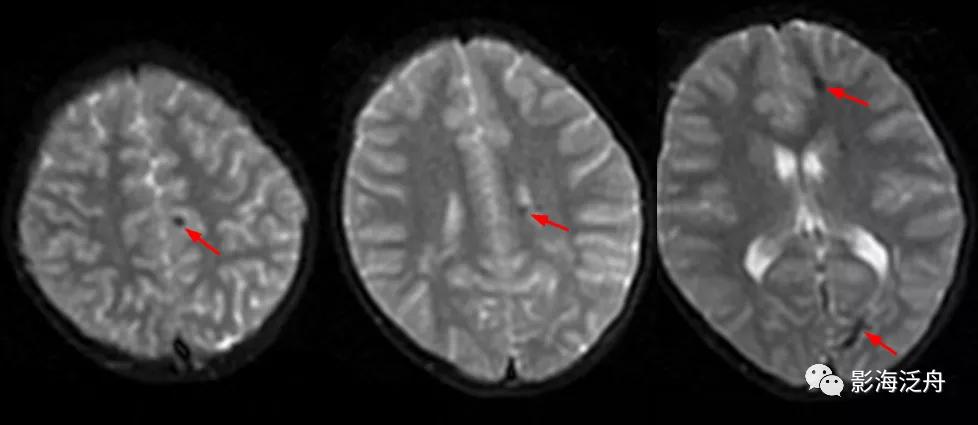

诊断虽然明确了,但故事到这里还没结束,回过头去看患者第一次检查的低b值DWI序列,可以发现这些病灶其实早就存在。但为什么第一次检查的时候没有及时发现呢?想必这大概率是因为大家对低b值DWI序列认识不足导致的,尤其是低年资诊断医生和神经科临床医生往往会自动忽略掉低b值DWI序列,再或者就是把低b值DWI误认为是高b值DWI序列。

在低b值DWI序列可以看到左侧大脑半球多发磁敏感伪影(红箭)。

从理论上讲,无论高b值DWI还是低b值DWI序列都应该对磁敏感伪影很敏感,但实际情况是不是这样呢?看下图↓↓

上图可以发现,在低b值DWI序列上左侧额顶叶交界区的病灶显示清晰(红箭),但在高b值DWI序列上,除病灶外,多个脑沟也表现出磁敏感伪影(绿箭)。因此,当病灶足够小或者数量比较少的时候很难区分到底是伪影还是病灶,而低b值DWI序列可以较好地解决这一问题。